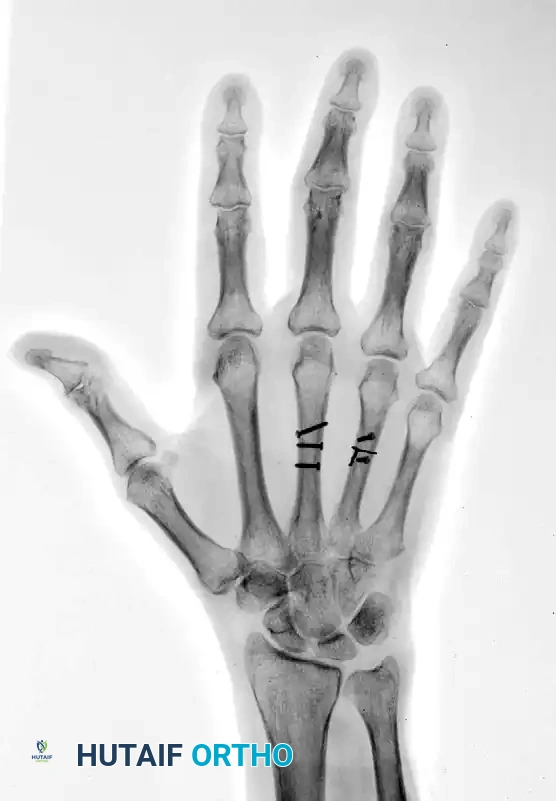

Preoperative Imaging:

FIGURE 67-42 A: Preoperative AP radiograph showing shortened and oblique middle and ring metacarpal fractures.

FIGURE 67-42 B: Preoperative oblique radiograph demonstrating the fracture geometry, which is highly suitable for interfragmentary fixation.

Postoperative Imaging:

The fractures were reduced anatomically. Lag screws were placed to provide interfragmentary compression. To neutralize the sagittal bending moment—particularly in the ring metacarpal—a supplemental 24-gauge cerclage wire was applied.

FIGURE 67-42 C: Postoperative AP radiograph showing anatomic reduction and rigid fixation.

FIGURE 67-42 D: Postoperative oblique radiograph. Note that the sagittal bending moment of the ring metacarpal shaft fracture was successfully offset by the supplemental 24-gauge cerclage wire fixation.